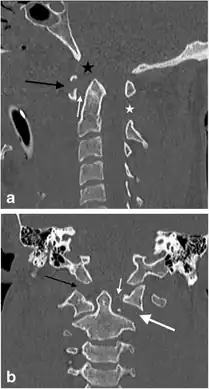

a,b)Jefferson’s fracture in a male victim of a motor vehicle accident